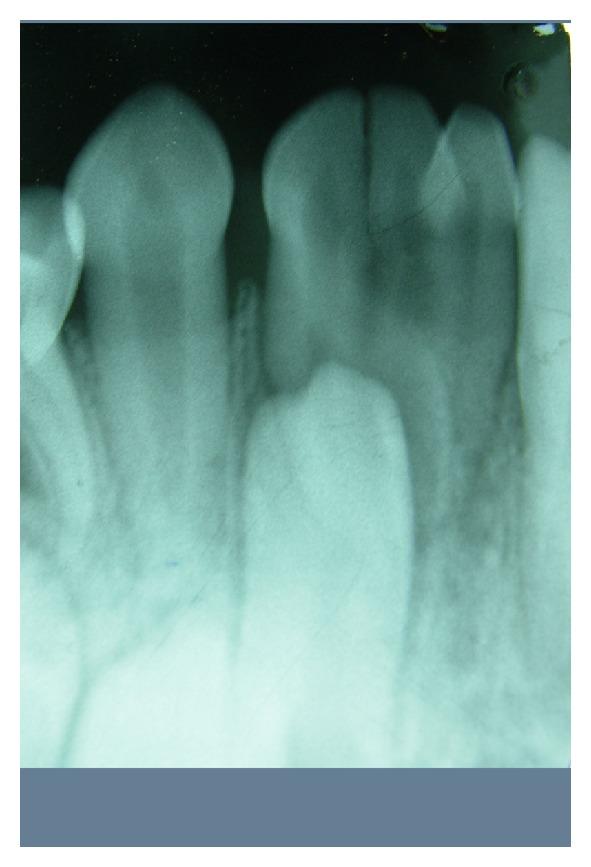

Fusion or synodontia is a union of two or more than two developing teeth. Commonly fusion occurs between teeth of the same dentition, mixed dentition, or between normal and supernumerary teeth. Fused primary teeth present with several clinical problems like caries, periodontal problem, arch asymmetry, delayed eruption, ectopic eruption of succedaneous teeth, aesthetic, and other complications. This paper presents a rare and unusual case of triple teeth in mandibular primary dentition.

https://cdn.ncbi.nlm.nih.gov/pmc/blobs/a727/3533612/9a1bd3c8c62e/CRIM.DENTISTRY2012-735925.001.jpg